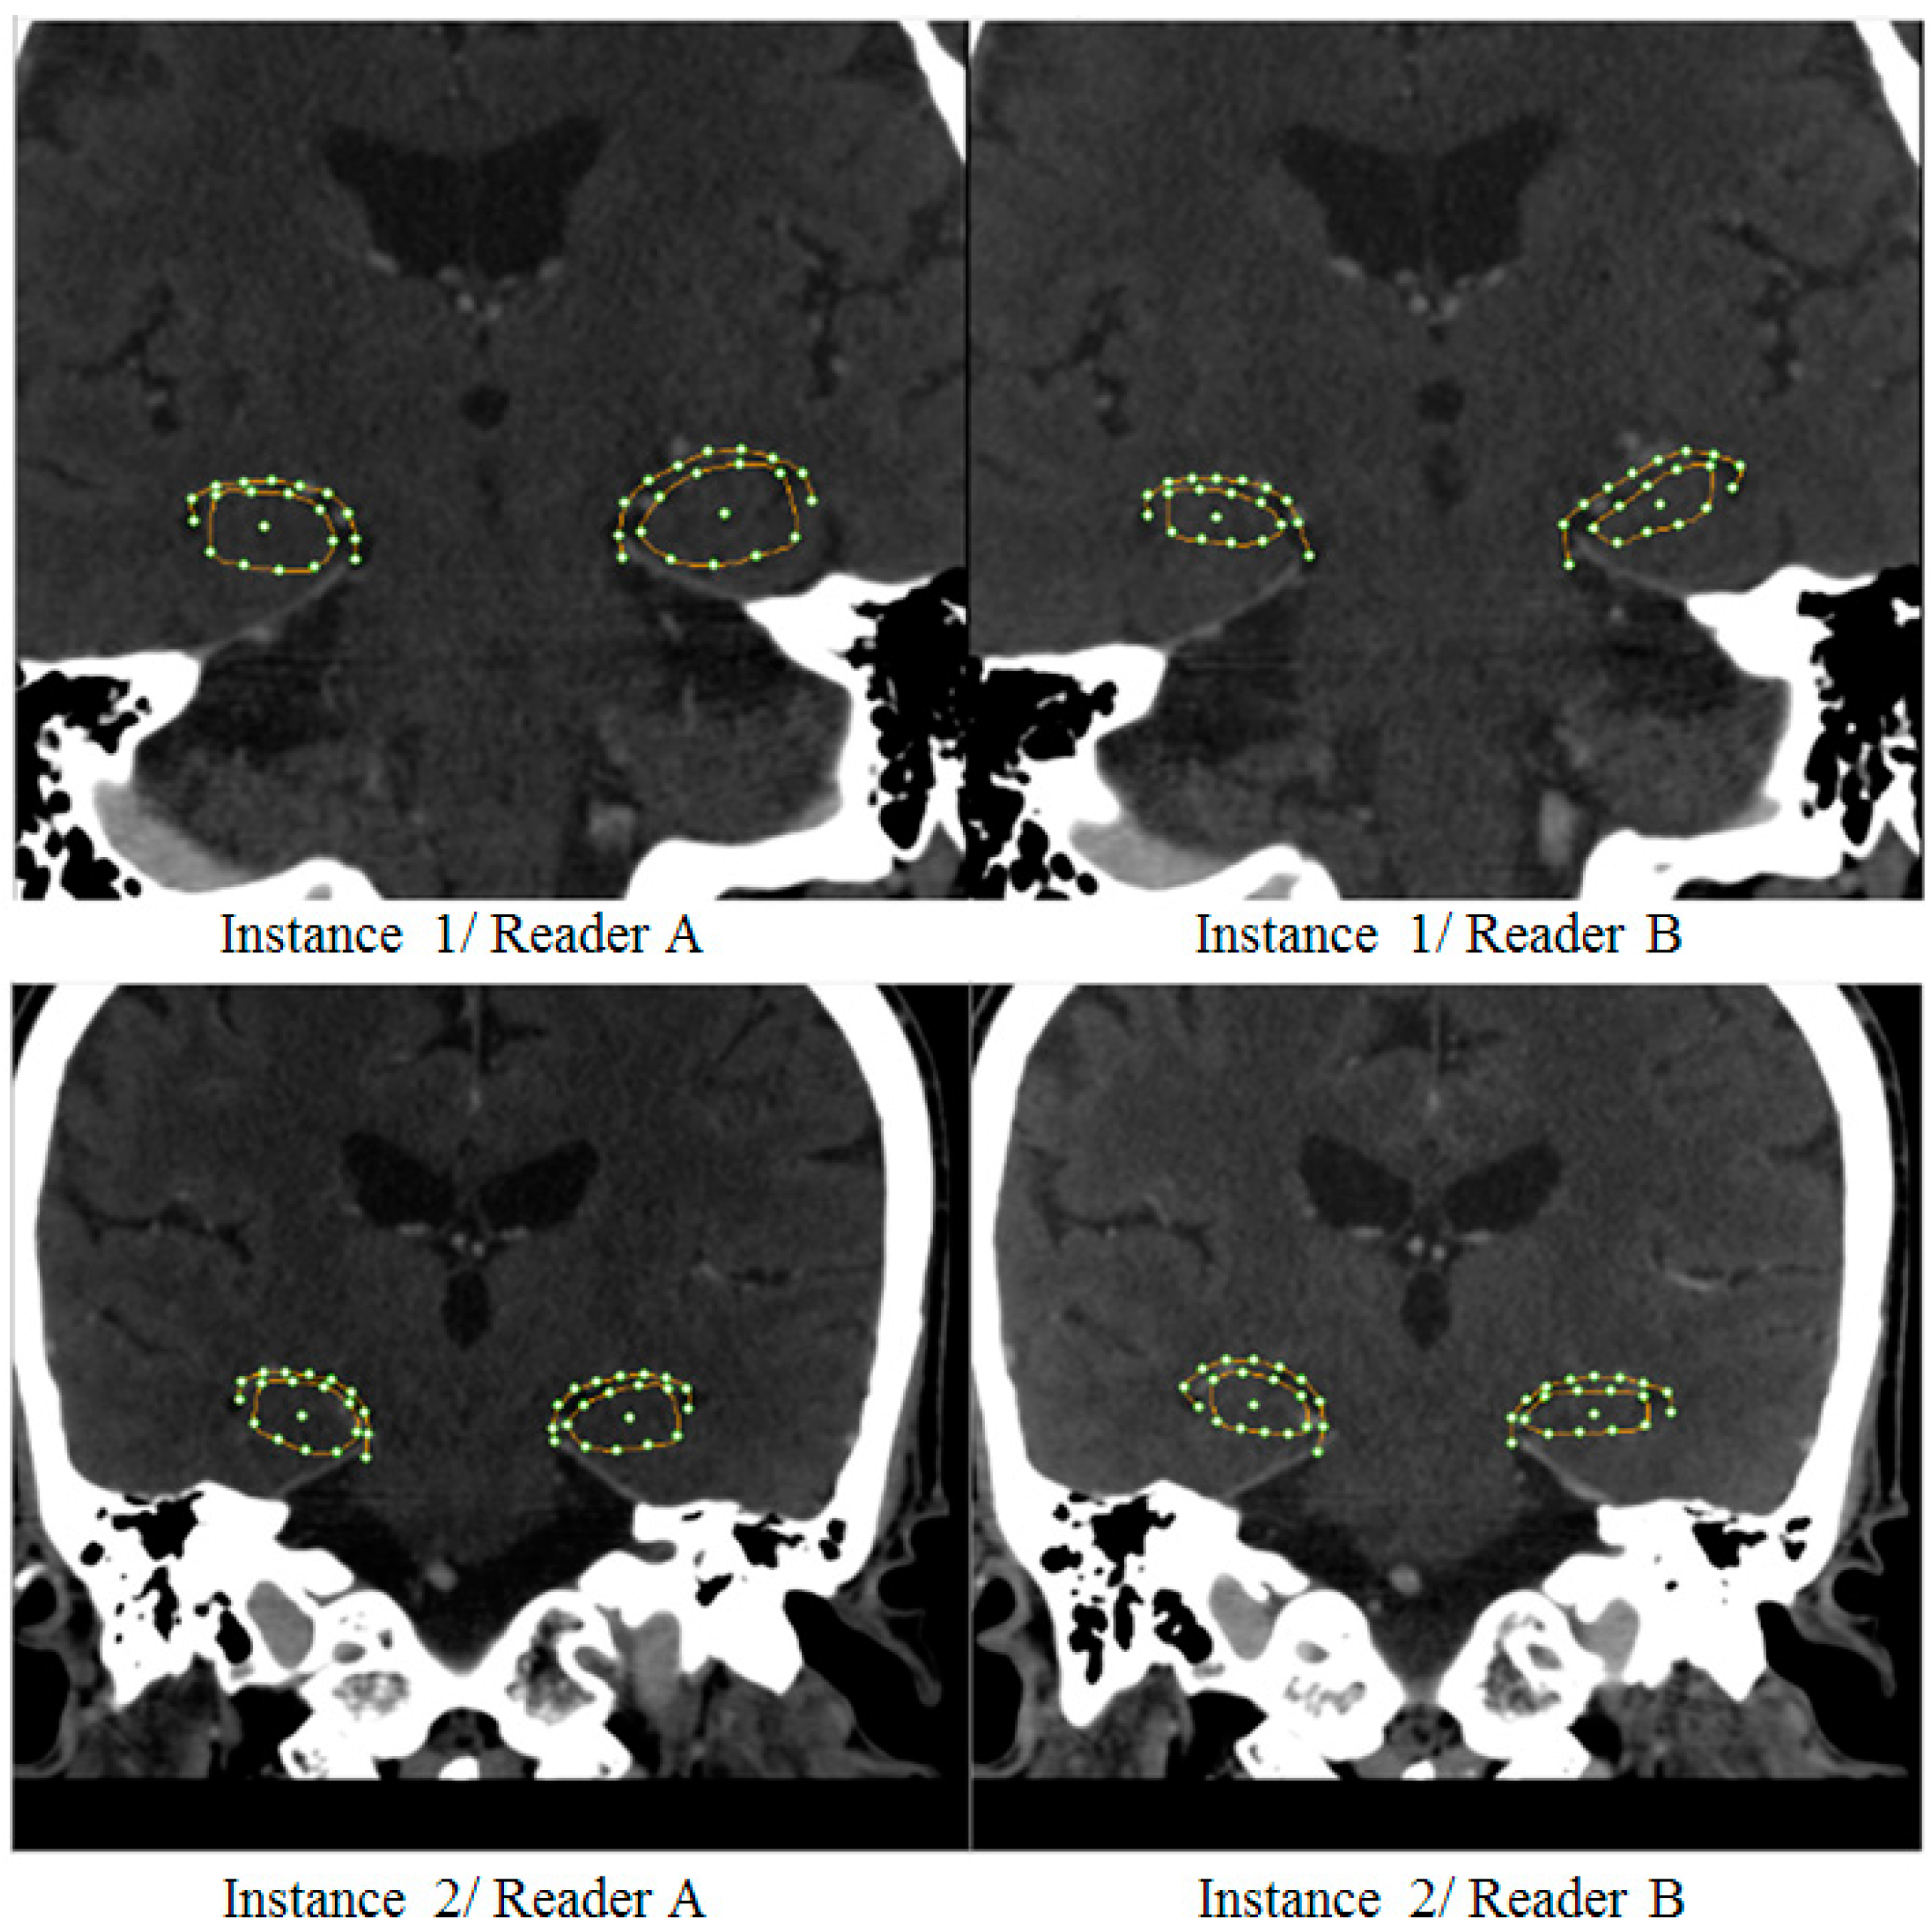

2.2. Imaging Protocol

2.3. SSA Software

3.1. Hippocampal Morphology Variability